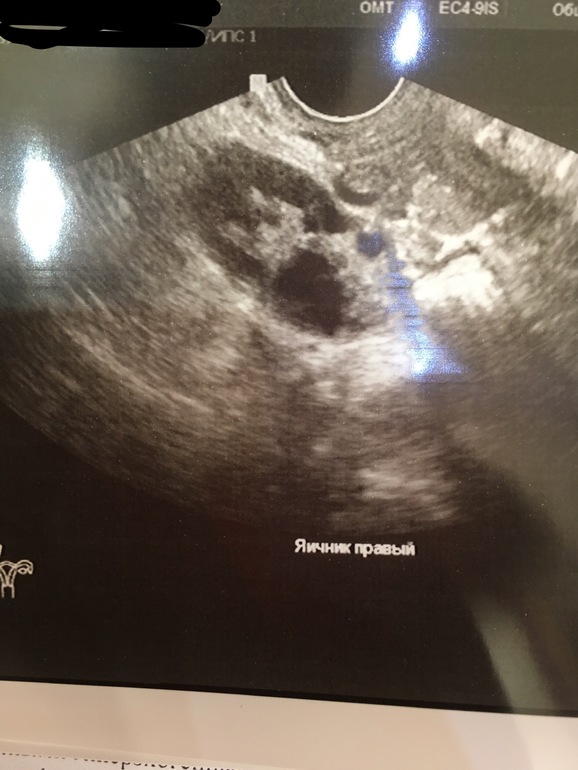

Там же в заключении написано, что подозрение на эндомеирмоидную кисту и плюс второй яичник мультифолликулярный. В теле матки подозрение на аденомиоз и в шейке матки какая то киста. Вам к врачу нужно, это не овуляция.

Вам к врачу надо. На вид МФЯ и полипы цервикального канала.

с МФЯ ничего не делают,он в целом не страшен. Полипы удаляют гистероскопически, под общим наркозом.А могут сказать и не трогать, наблюдать. Идите лучше к врачу.